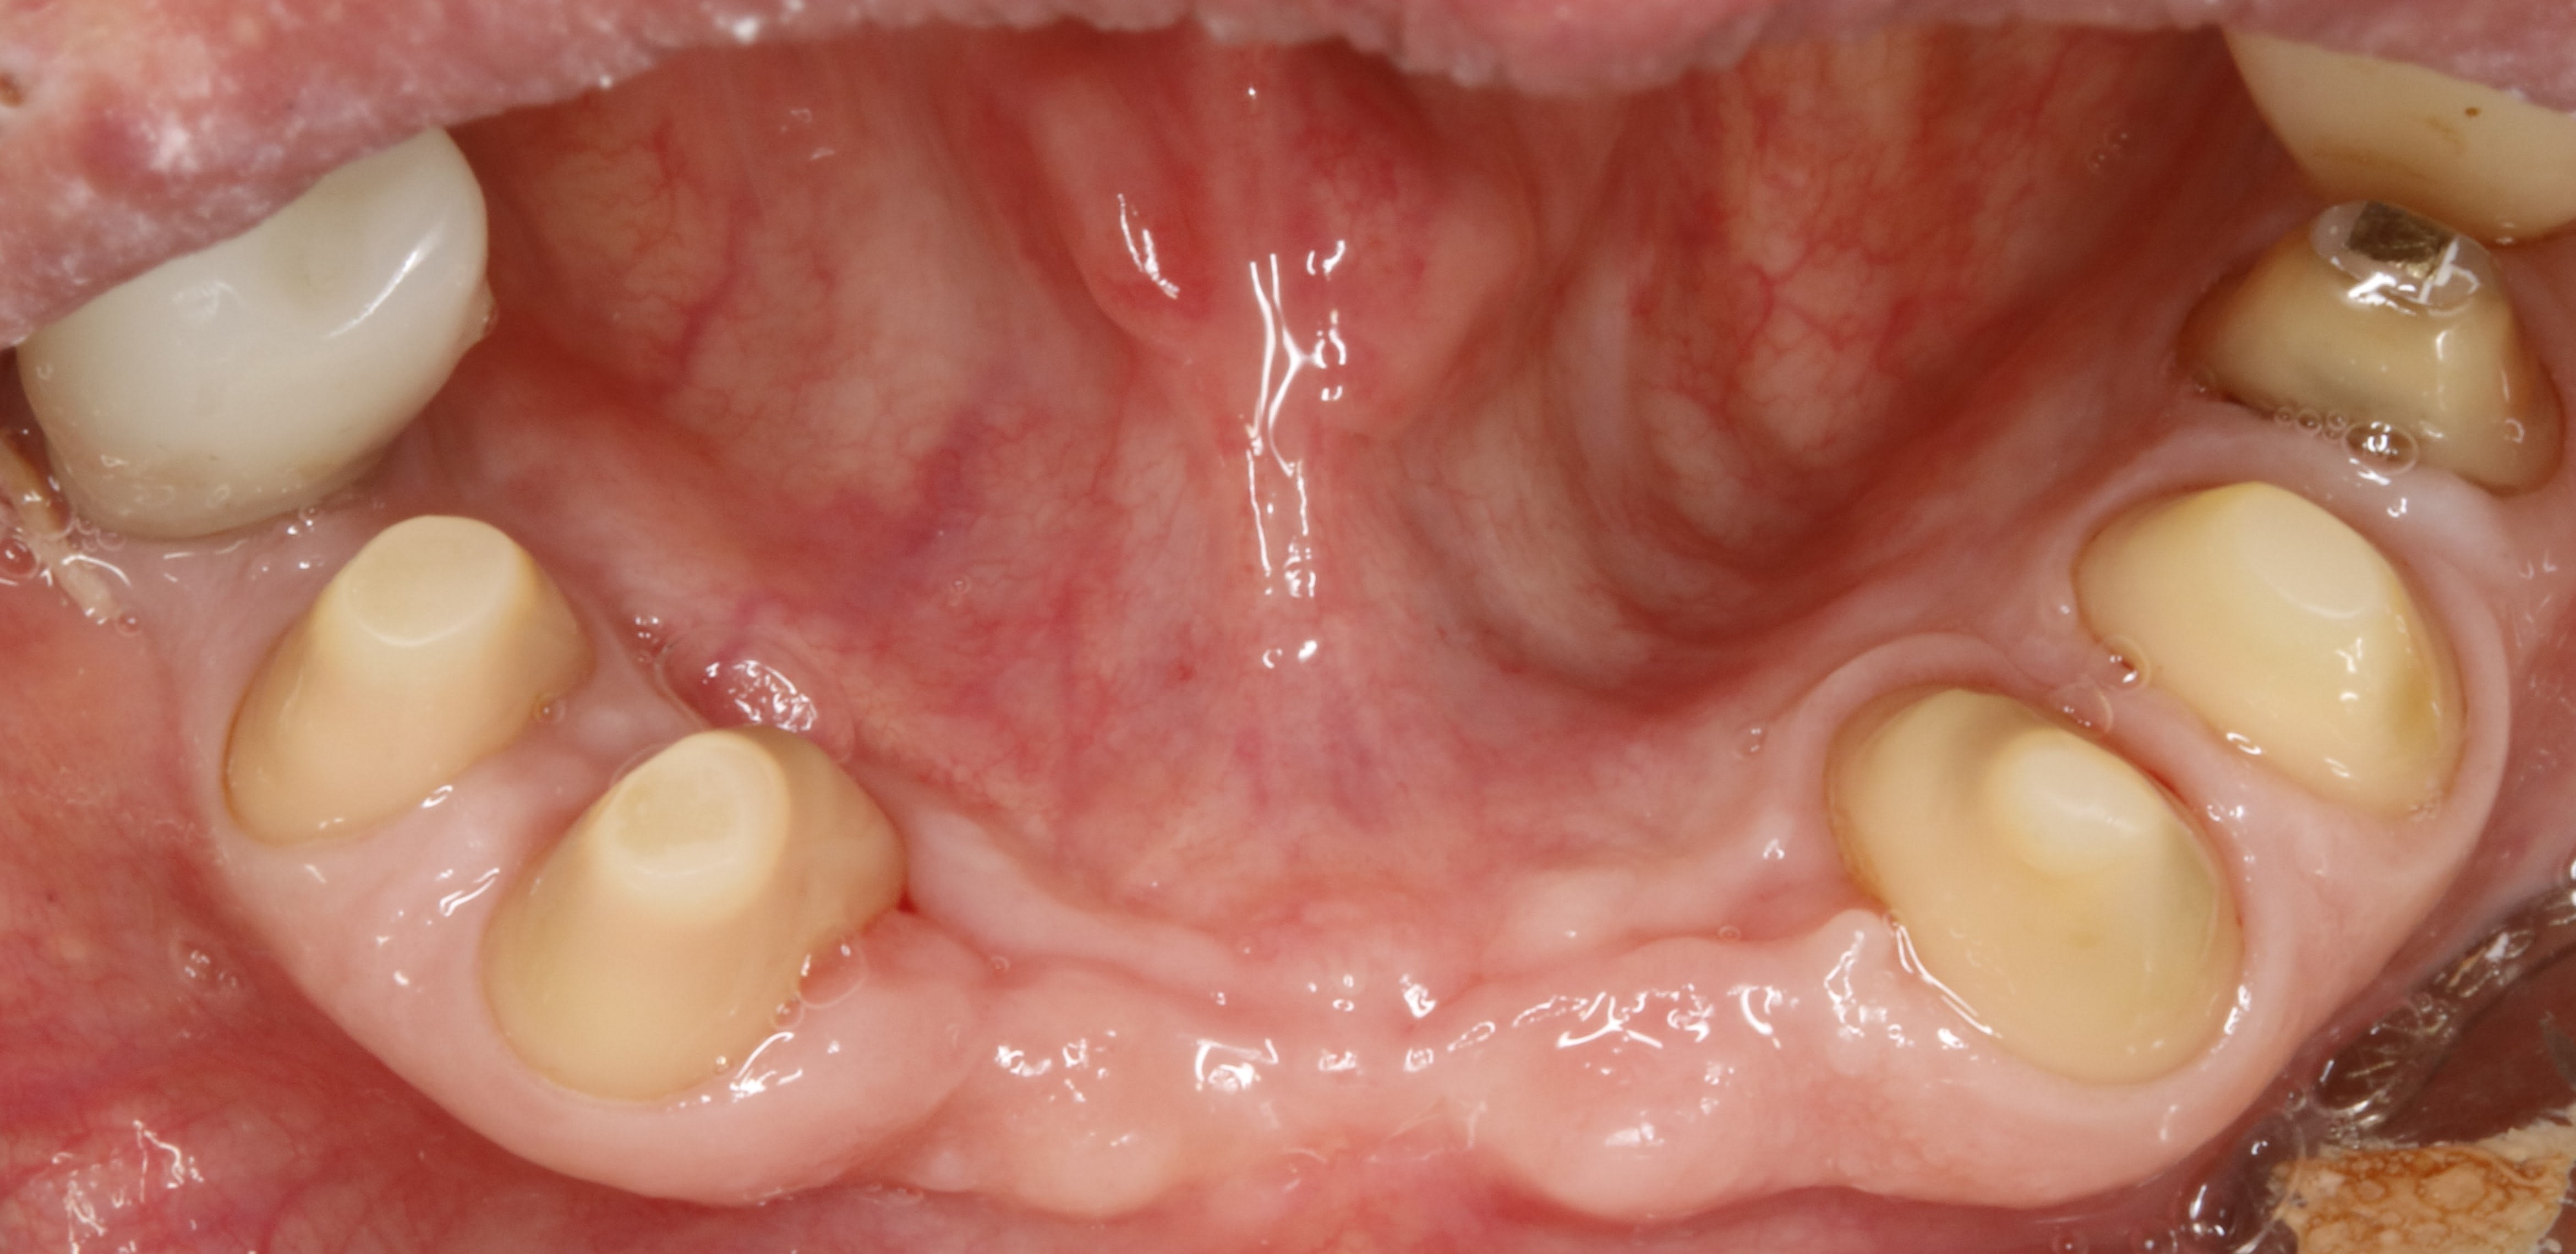

tourne et vire y a que ça qui me plait , le bridge de contention du bas .

toutes les dents qui bougent à mort , les incisives qui se font la malle , les gencives explosées et gros pb occlusal bien sur .

apres extractions et endos zing zing les tailles .

ici les tailles ont duré 3 mois pour en arriver là .

3 mois pour tailler .

non , on va le dire différemment, 3 mois pour arriver au niveau des limites définitives .

Chaques fois un petit coup pour arriver au niveau gingival cicatriciel du jour .

4 fois y compris les prétailles en unitaire avant les extractions de 41,42, 31,32 et 46

dans les 4 fois , en plus des tailles des moignons en totalité je compte aussi les tailles des racines et de gencive qui me permettent de faire de l assainissement parodontal .